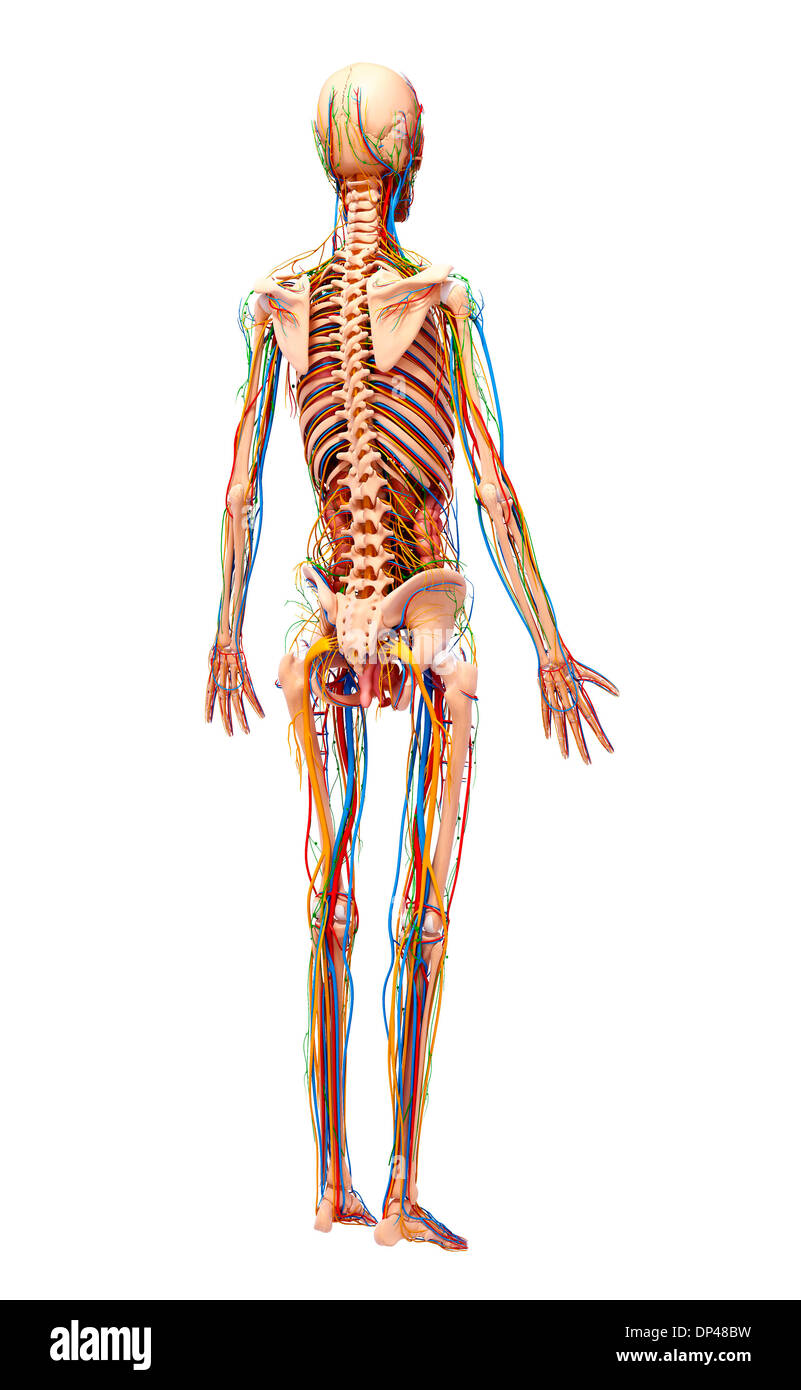

, Artwork Banque D'Imageshttps://www.alamyimages.fr/image-license-details/?v=1https://www.alamyimages.fr/artwork-image65261727.html

, Artwork Banque D'Imageshttps://www.alamyimages.fr/image-license-details/?v=1https://www.alamyimages.fr/artwork-image65261727.htmlRFDP4WYY–, Artwork